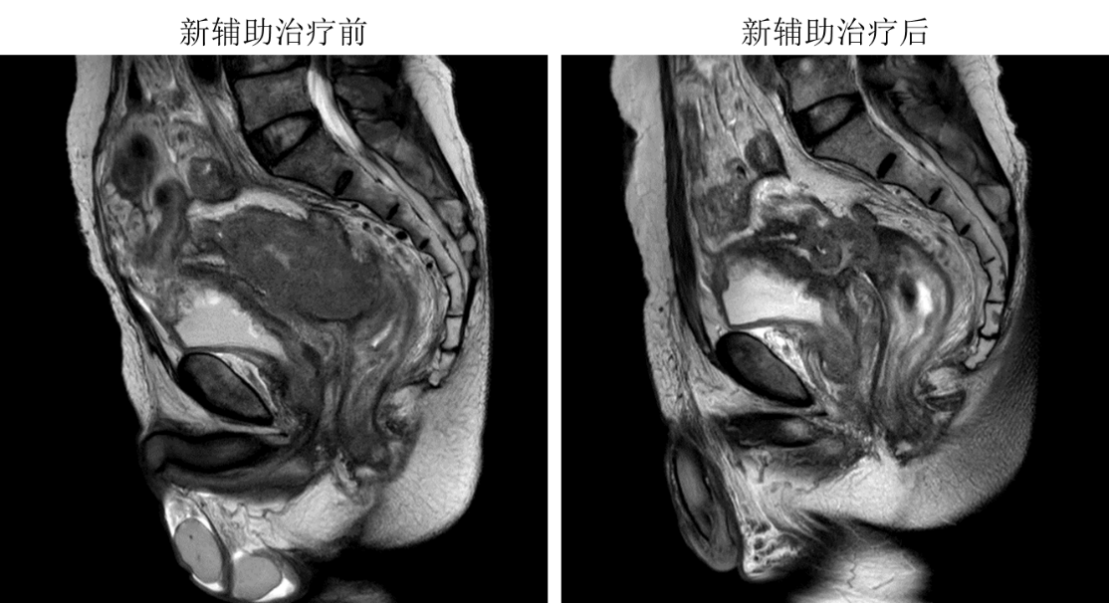

经过3月盆腔新辅助放化疗联合免疫治疗,患者局部晚期直肠癌较前缩小,邱健主任医师、刘瑞廷主任医师团队联合泌尿外科姜亚卓主任医师为患者安全实施了全盆腔脏器切除术,患者术后未出现并发症,恢复康复出院。